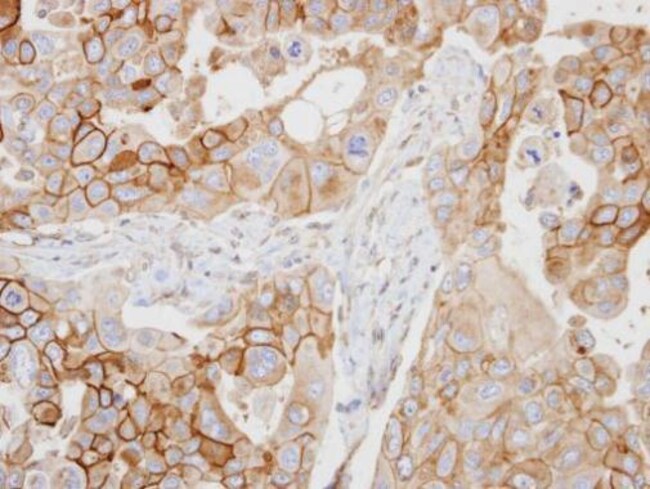

CD97 Polyclonal Antibody, Invitrogen™

Rabbit Polyclonal Antibody

Recommended positive controls: A549, HeLa, HepG2, HCT116. Store product as a concentrated solution. Centrifuge briefly prior to opening the vial.

CD97 is a G-protein-coupled seven-span transmembrane adhesive receptor that is constitutively expressed on granulocytes and monocytes and rapidly upregulated on T and B cells upon activation. CD97 is produced in alternatively spliced forms and its cellular ligand is CD55 (DAF), which protects various cell types from complement-mediated damage. Interaction of CD97 on leukocytes and CD55 on vessel cells probably facilitate leukocyte activation and migration into the tissues, similarly, CD97 seems to play a role in tumour migration and invasiveness. CD97 is involved in T cell regulation and peripheral granulocyte homeostasis.

Immunocytochemistry, Immunohistochemistry (Paraffin), Western Blot